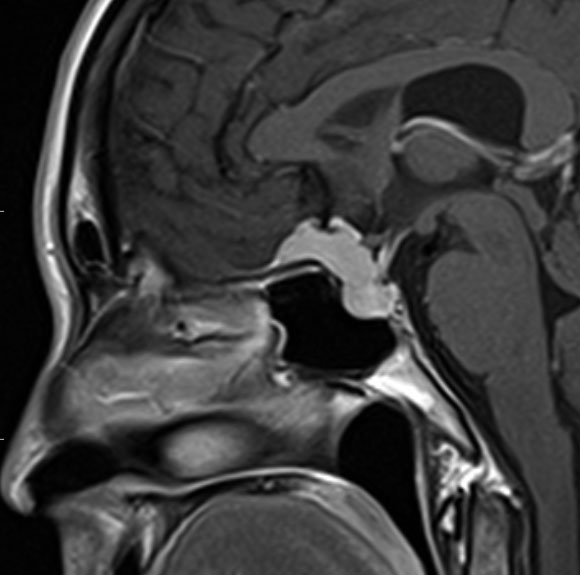

30代の女性に発生した髄膜腫です,一見すると松果体細胞腫と見分けはつきません。右の画像に見られるように典型的な中脳水道狭窄を生じていました。

軽度の閉塞性水頭症もありますが,頭痛も無く無症状なので経過を観察しました。髄膜腫だと診断できるのは,右の画像で見られるようにガレン大静脈が右側に偏っているからです。松果体細胞腫の場合は,ガレン大静脈は上方に変位します。

1年間経過観察したら水頭症が進行して脳室が拡大,腫瘍のサイズも大きくなりました。右側の画像で見られるようにガレン大静脈の左側のテントの下面から発生した髄膜腫でした。

左は手術直後の画像です,手術は左側のテント下面を見るために,後頭部経テント法 OTA occipital transtentorial approach で,小脳テントの左側を切断して腫瘍を全摘出しました。右側は6年後の画像ですが,腫瘍再発はありません。